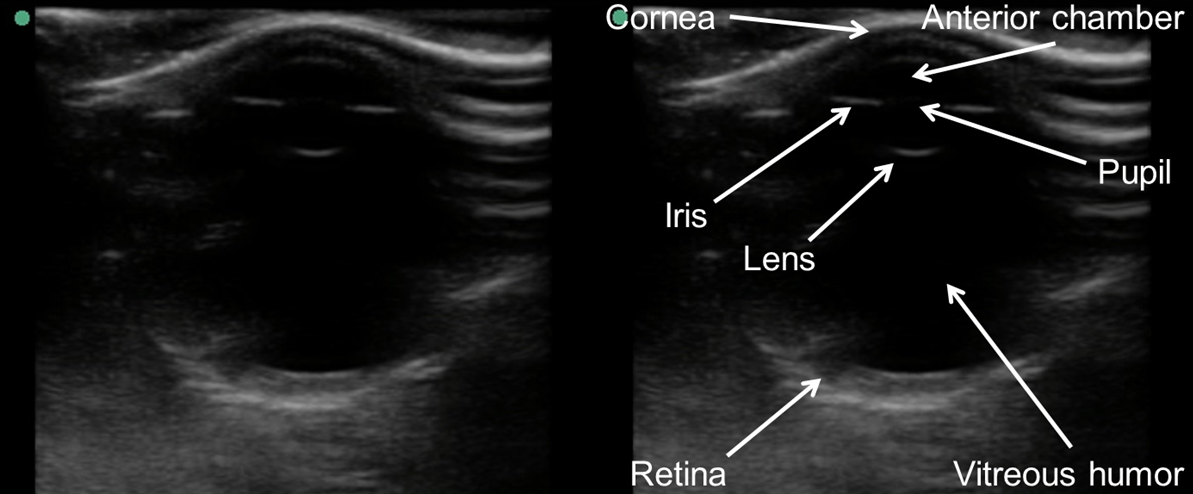

Ocular

Ocular ultrasound (Figure 29) can be used to evaluate for ocular pathologies such as foreign body, lens dislocation, vitreous hemorrhage and retinal detachment (REF. 5). Additionally, ultrasound can be used to evaluate patients with potentially increased intracranial pressure by evaluating the optic nerve sheath diameter.

Figure 29. Transverse image of eye demonstrating anatomy (Image courtesy of Matthew Lohse, MD. Baylor Scott & White-Temple).